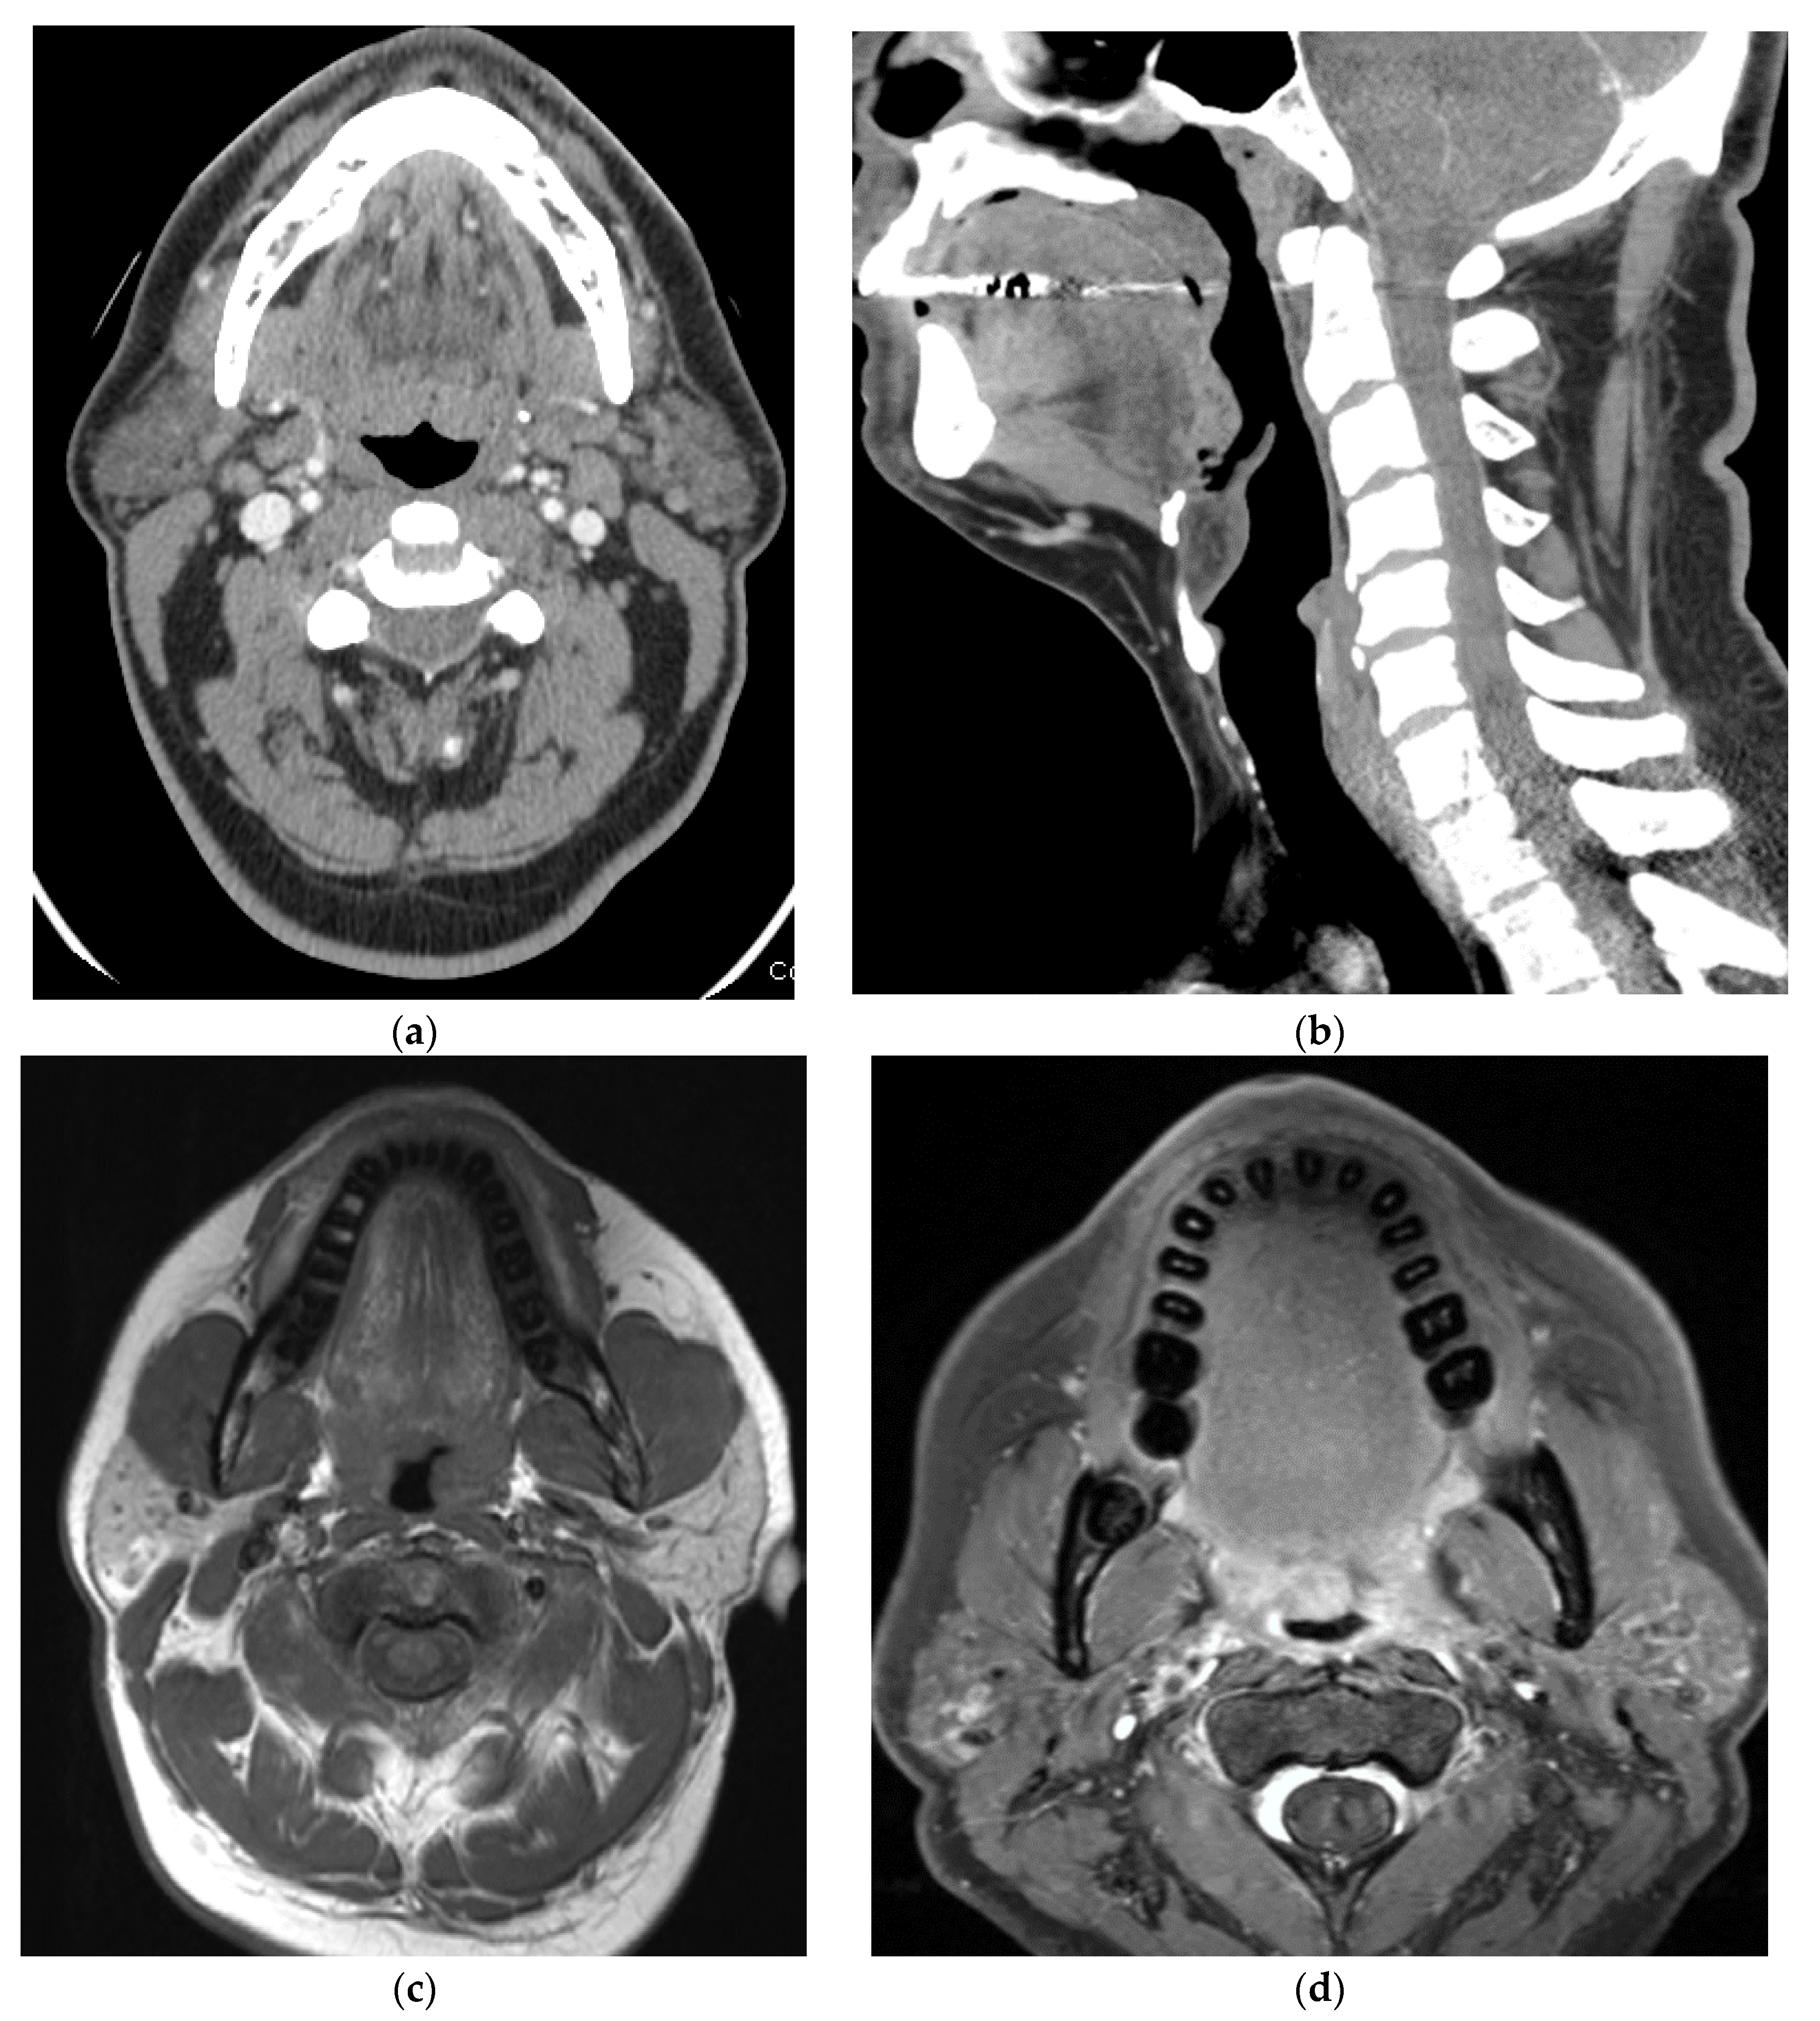

5. Imaging of Oropharyngeal Cancers

6. Staging of Oropharyngeal Cancers